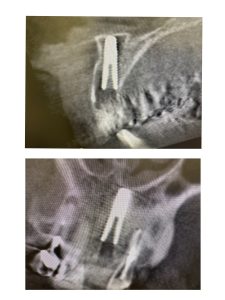

朝2より、前歯抜歯即時、ソケットシールド併用

仮歯まで!最近は切開はしない!

来週のオペ左右前歯2本、破折に病巣

即時荷重予定、固定を獲得しなければならない、18ミリ予定